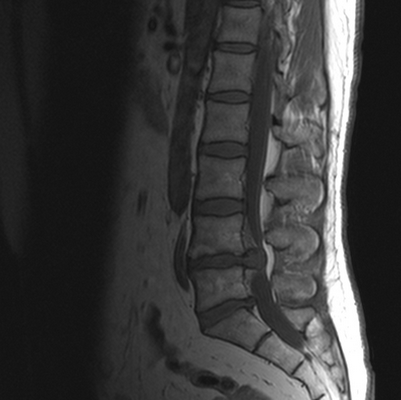

Грыжи дисков - общий термин, отражающий смещение диска. До 90% грыж дисков наблюдаются на уровне двух нижних поясничных сегментов. МРТ поясничного отдела позвоночника служит методом выбора для их диагностики.

МРТ поясничного отдела позвоночника. Парамедиальная грыжа (экструзия) диска L5/S1 слева с компрессией экстрадурального сегмента корешка. Сагиттальная и аксиальная Т2- взвешенные МРТ.

Сопоставление размеров и расположения грыж, определяемых при МРТ, с болевым синдромом показывает,что нет прямой связи между болевым синдромом и величиной грыжи. До 30% грыж видимых при МРТ позвоночника бессимптомные. Нет и прямой связи между болевым синдромом и размером позвоночного канала. В то же время, вокруг грыжи, по данным МРТ позвоночника, формируется грануляционная ткань а костном мозге смежных позвонков наблюдается асептический спондилит, что говорит о большом значении воспалительного процесса.